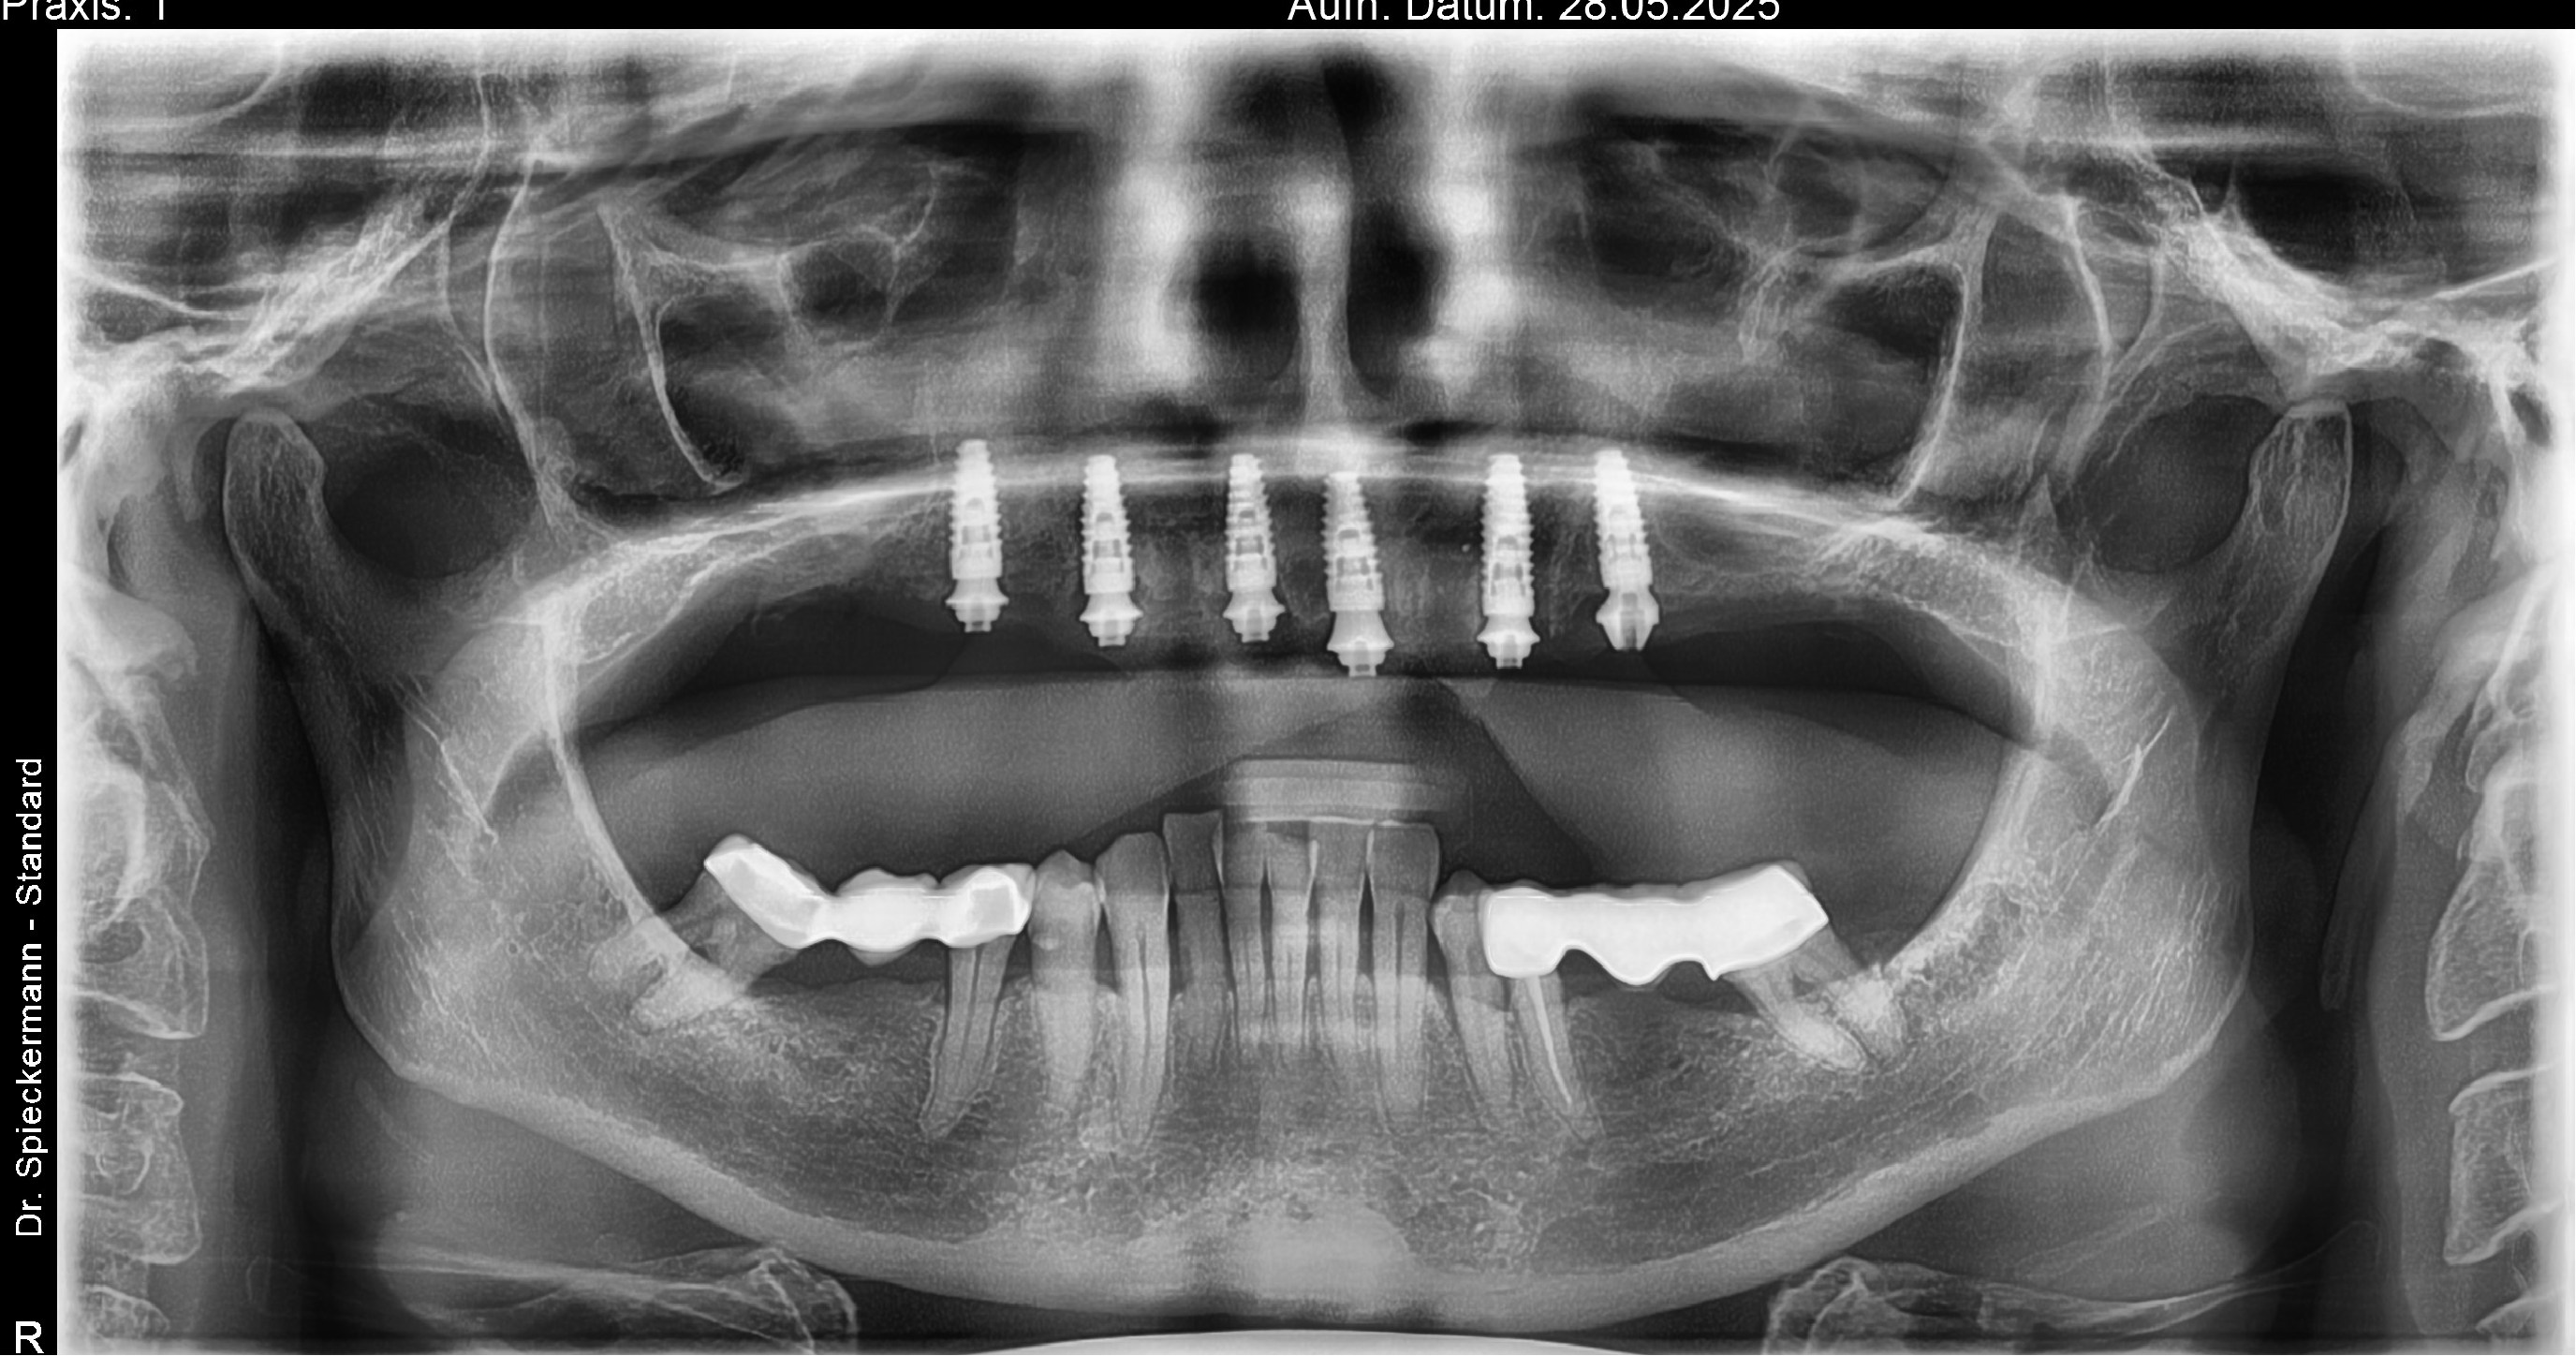

Initial diagnostics included CBCT imaging and full-arch intraoral scanning. A digital wax-up with an increased vertical dimension of approximately 2 mm was created to simulate functional and aesthetic improvements. Fully digital implant planning was carried out, and a SMOP tooth supported guide was designed, anchored in the region of the lateral incisors.

Following the extraction of teeth 13–23, the tooth-supported guide was positioned and stabilized, allowing precise, fully guided implant surgery. Multi-Unit Abutments were inserted according to the digital plan. Immediately post-surgery, intraoral photogrammetry was performed to record the implant positions with high accuracy, eliminating the need for conventional impressions or splinting.

Healing progressed without complications. Stable peri-implant soft tissues and successful osseointegration were observed. After removal of the provisional restoration, a second intraoral photogrammetry scan was performed to document the implant positions at the time of prosthetic release. These data were transferred to the patient’s general dentist for final restoration fabrication.